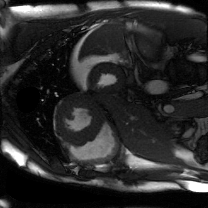

Supervised Deep-Learning (DL)-based reconstruction algorithms have shown state-of-the-art results for highly-undersampled dynamic Magnetic Resonance Imaging (MRI) reconstruction. However, the requirement of excessive high-quality ground-truth data hinders their applications due to the generalization problem. Recently, Implicit Neural Representation (INR) has appeared as a powerful DL-based tool for solving the inverse problem by characterizing the attributes of a signal as a continuous function of corresponding coordinates in an unsupervised manner. In this work, we proposed an INR-based method to improve dynamic MRI reconstruction from highly undersampled k-space data, which only takes spatiotemporal coordinates as inputs. Specifically, the proposed INR represents the dynamic MRI images as an implicit function and encodes them into neural networks. The weights of the network are learned from sparsely-acquired (k, t)-space data itself only, without external training datasets or prior images. Benefiting from the strong implicit continuity regularization of INR together with explicit regularization for low-rankness and sparsity, our proposed method outperforms the compared scan-specific methods at various acceleration factors. E.g., experiments on retrospective cardiac cine datasets show an improvement of 5.5 ~ 7.1 dB in PSNR for extremely high accelerations (up to 41.6-fold). The high-quality and inner continuity of the images provided by INR has great potential to further improve the spatiotemporal resolution of dynamic MRI, without the need of any training data.

翻译:在这项工作中,我们建议了一种基于IRI的方法,用这种方法来改进动态磁共振感应成像(MRI)重建,而该方法只是以高度低劣的 k-空间数据为基础,而该数据仅以磁共振坐标作为投入。具体地说,拟议的IRI将动态MRI图像作为一种隐含功能来表示,并将其编码到神经网络中。网络的权重仅从稀有的(k, t)空间数据本身中学习,而没有外部培训数据集或先前的图像。 利用基于IRI的强有力隐含性稳定化,同时不以清晰的动态和时空坐标坐标坐标坐标坐标作为投入。 拟议的IRIR将动态MRI图像作为一种隐含功能,将其编码到神经网络中。网络的权重仅从淡化的(k, t)空间数据本身学习,而没有外部培训数据集或先前的图像。